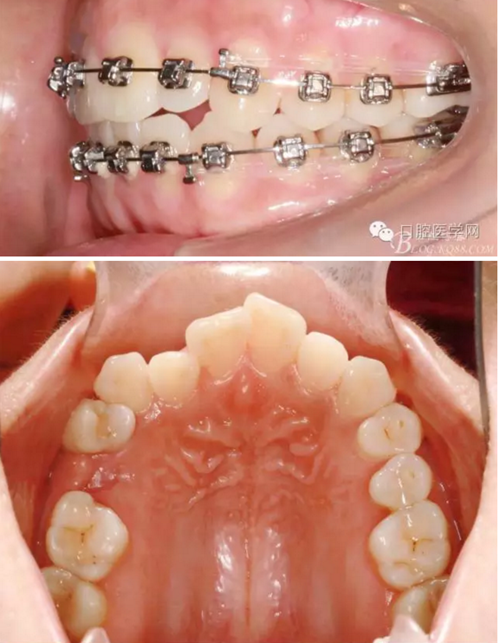

37,45缺失后,鄰牙近中移動(dòng)占據(jù)了部分牙位;患者要求減少治療費(fèi)用,不做種植修復(fù),那怎么協(xié)調(diào)右側(cè)的咬合關(guān)系?

15是根管治療過(guò)的牙齒,只好忍痛舍去......

在滿足功能的前提下,退而求其次...有時(shí)候,正畸醫(yī)生不得不妥協(xié)。